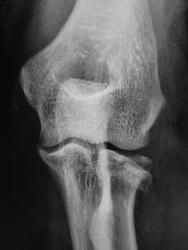

Киста и перелом с неизвестной давностью.

На счет кисты сомнительно, зона физиологического разряжения. Перелом, похоже, свежий.

"Рентгенанатомия скелета", Лагунова "...Бугристость лучевой кости, располагающаяся на ее внутренней поверхности, в таком положении выглядит груботяжистой, тогда как на остальном протяжении рисунок структуры мелкопетлистый. Основание бугристости иногда проецируется в виде очень четко очерченного овального просветления, которое может быть принято за очаг деструкции."

Дорогая Олечка, бугристость - да, эндост - не совсем.

Травма в 7.30. Снимок сделан в 11.15.